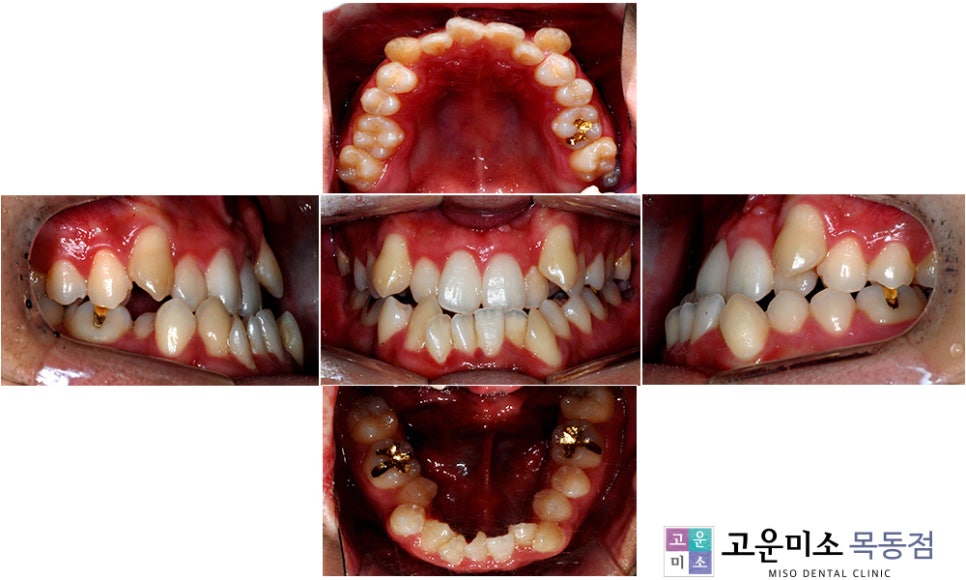

이 환자분은 만 24세의 남성으로,

아래턱이 돌출되어 주걱턱에 대한 고민을 하신 후,

입 안의 공간이 협소하여 치아 배열이

많이 어긋나 있고, 옆모습을 보면

윗입술이 아랫입술을 덮지 않고

오히려 아래턱이 나와 있어 아랫입술이 돌출된

주걱턱의 전형적인 형태를 보입니다.